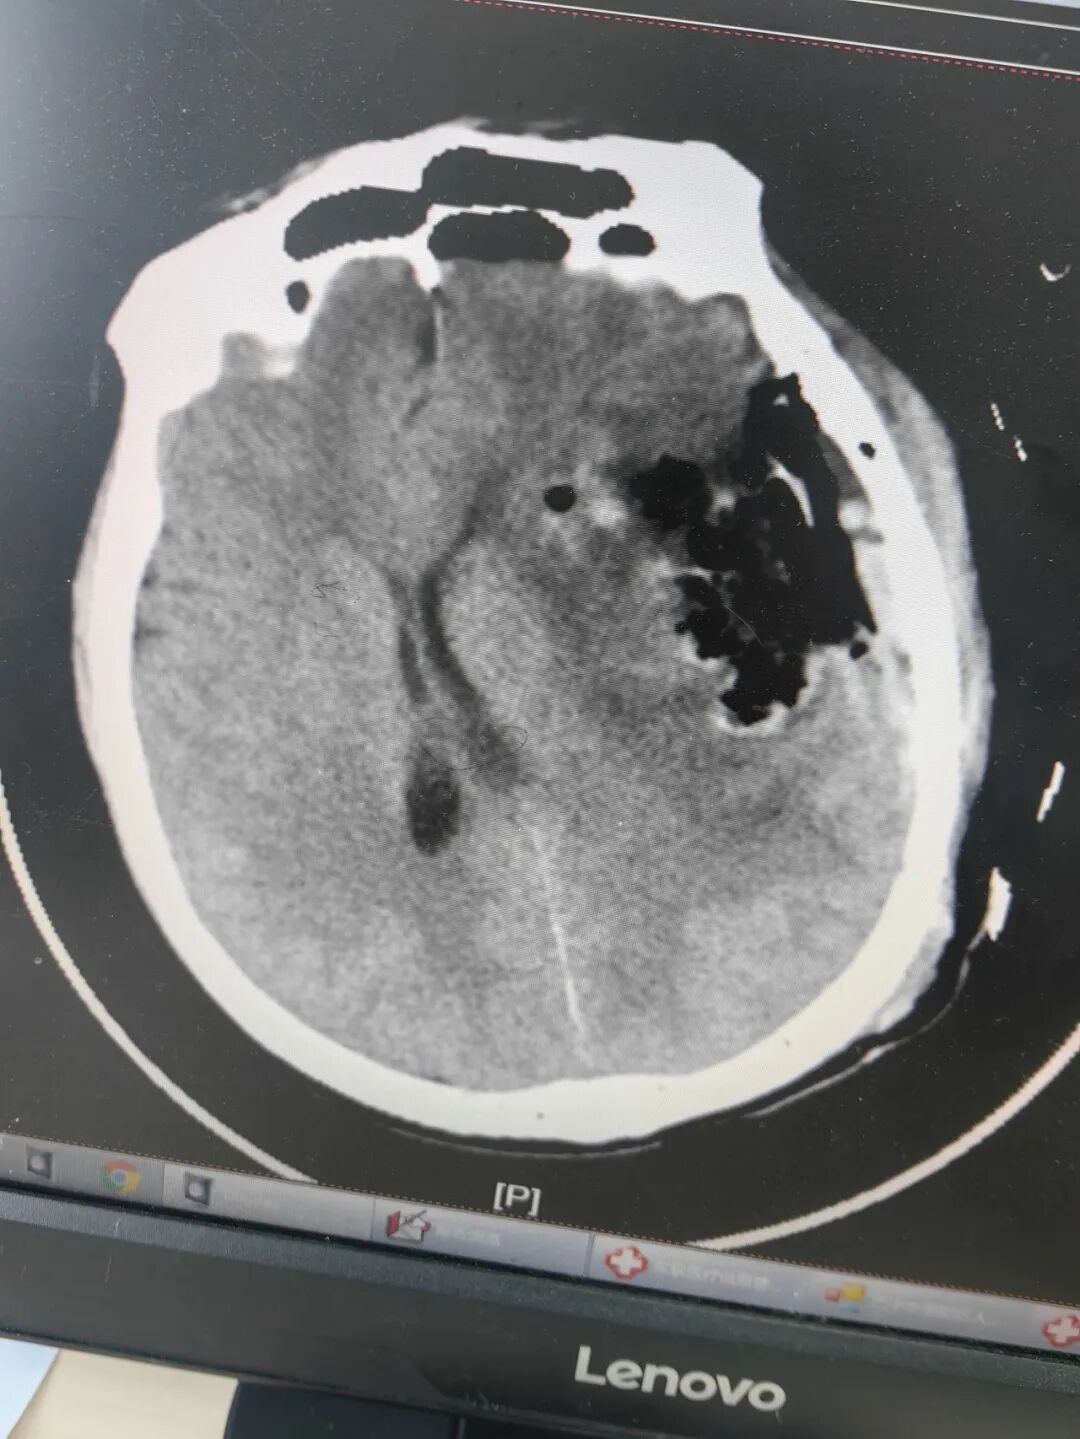

58岁的男性患者马先生因“突发意识障碍伴肢体反复抽搐1小时”被紧急送往恩阳区人民医院急诊科。情况万分危急,医院立即开通绿色通道。经急诊CT及核磁共振检查提示:患者左侧颅内长有一个巨大肿瘤,大小约6.7x5.8x4.5cm,这不仅是导致患者意识障碍和癫痫的元凶,更随时可能引发脑疝,危及生命。

术前影像